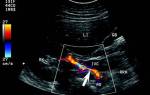

- ЭКГ или УЗИ сердца;